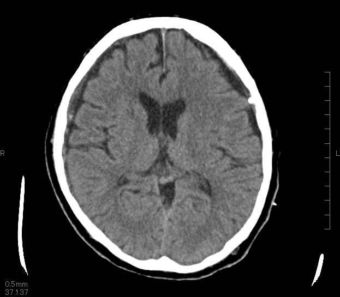

06 慢性硬膜下血腫 穿頭血腫洗浄ドレナージ術

慢性硬膜下血腫(まんせいこうまくかけっしゅ)とは?

頭をぶつけたりした後、数週間してから血が溜まってくる不思議な袋状のかたまりです。

自然に治ることもありますが、大きい場合は手術が必要となります。

穿頭(せんとう)血腫洗浄ドレナージ術

1円玉サイズの穴を頭の骨に開けて、そこから細い管(ドレーン)を入れて中身の血性液を除去洗浄します。内容液を抜くために、ドレーンを残したまま傷を閉じます。ドレーンは翌日に抜去します。